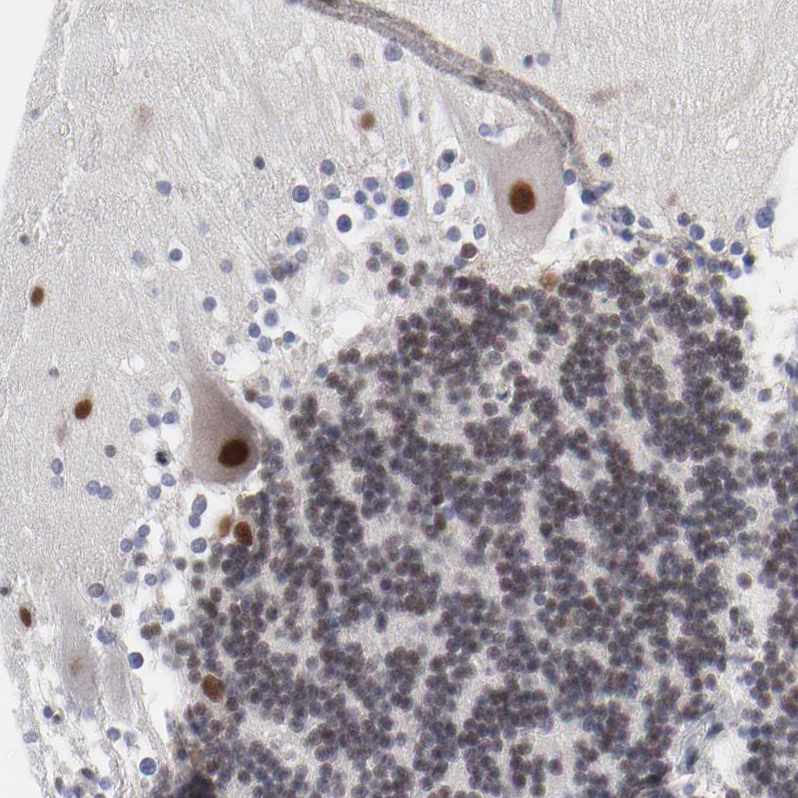

Immunohistochemical staining of human skeletal muscle shows moderate to strong nuclear positivity in myocytes.